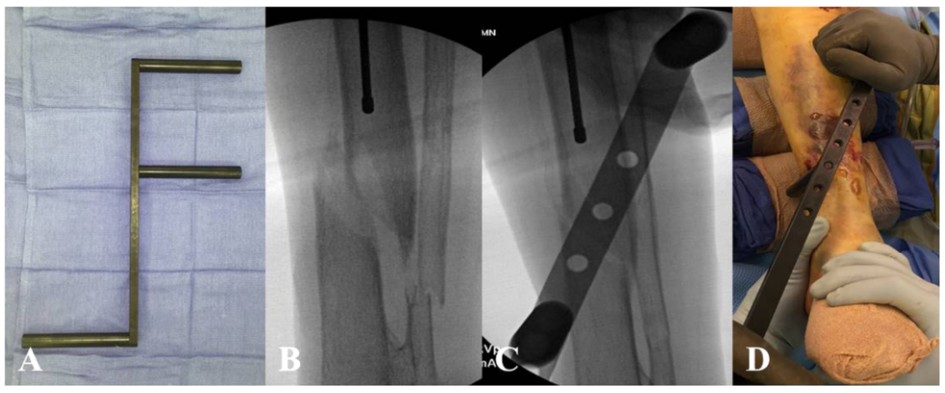

Маневры закрытой репозиции можно выполнить с помощью редукционного инструмента, такого как F-образный редукционный аппарат, F-образное рентгенографически передающееся редукционное устройство, которое корректирует углы инверсии/эксверсии, а также медиальное/латеральное перемещение (рис. 6).

Рис. 6. F-образный редуктор перелома, применяемый в хирургии.

Однако устройство может оказывать значительную нагрузку на мягкие ткани, поэтому следует избегать длительного использования этого устройства для перенастройки. Редукционные щипцы также можно накладывать чрескожно, как при спиральных и косых переломах. Эти инструменты можно применять безвредно для мягких тканей через небольшие разрезы (рис. 7).